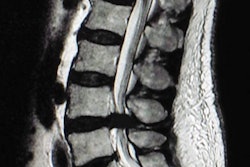

The Clinical Imaging Board (CIB) in the U.K. does not support self-referral for MRI exams or other diagnostic imaging, according to a position statement issued on 11 August.